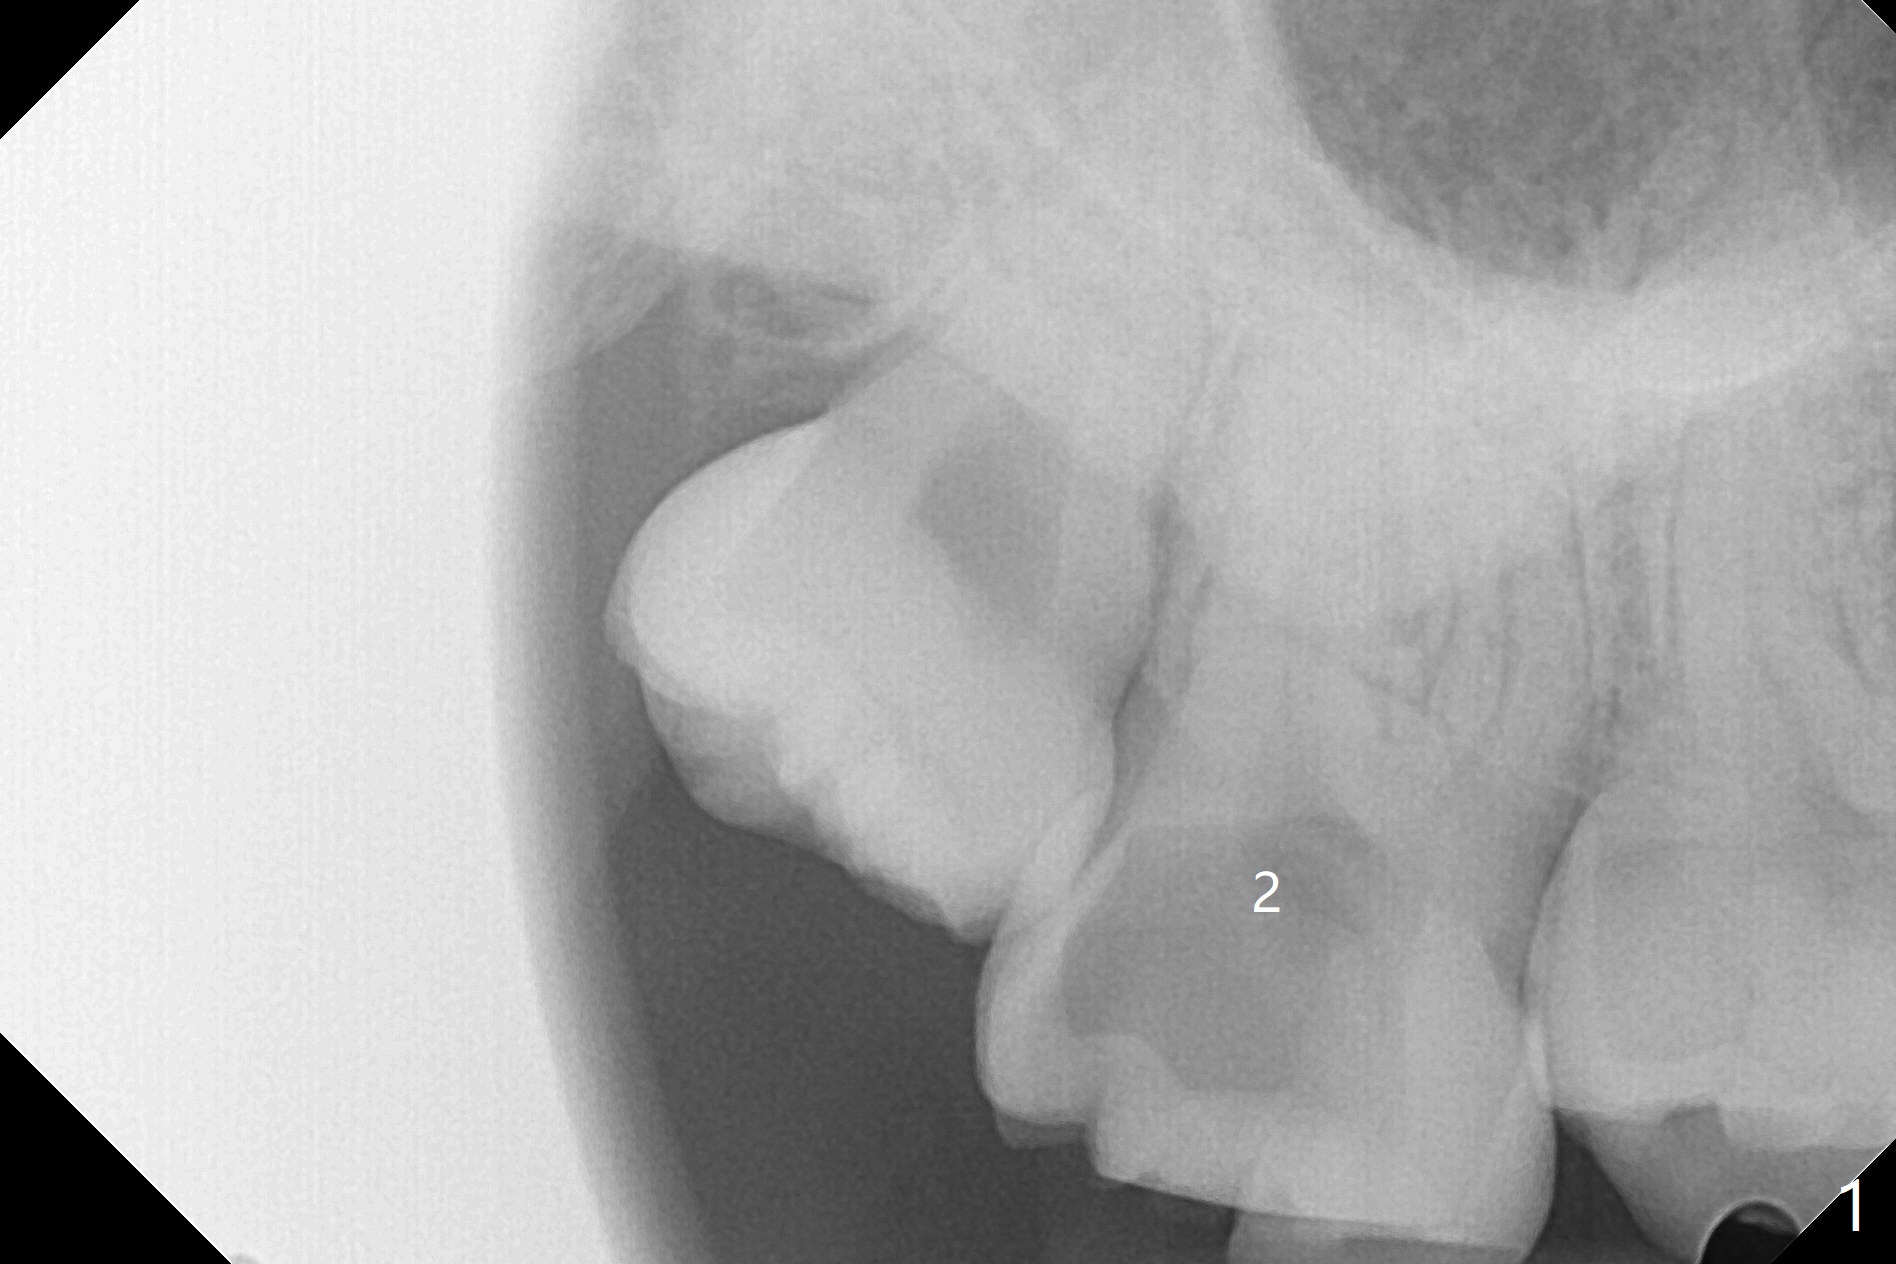

A 32-year-old nervous woman presents emergently with toothache at #2 with subgingival caries (Fig.1). She is unwilling to have #1 extracted. Vanilla graft and ß-TCP hydrated with GEM21S (Fig.2 *) are placed in the three sockets with distinct septa (good blood supply for regeneration). A 12x12 mm BioXclude is used to close the socket opening. After 4/0 PGA suture, periodontal glue is applied for retention of the suture and the membrane.